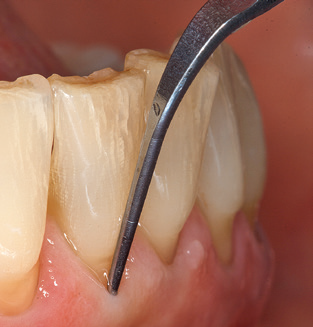

Als zentraler Bestandteil der UPT ist natürlich die Instrumentierung zum mechanischen Entfernen des Biofilms von vorrangiger Bedeutung. Der Ablaufplan einer UPT sieht zu diesem Zweck eine supra, ggf. auch eine subgingivale Reinigung vor. Hier hat sich im Rahmen unseres Konzepts eine Kombination von Handinstrumenten und maschineller Reinigung bewährt. Für die maschinelle Vorgehensweise gibt es mehrere Optionen: Schallgeräte, Ultraschallgeräte sowie Pulverstrahlgeräte.

Die gute Ausleuchtung des Arbeitsfeldes stellt eine wesentliche Erleichterung dar. Bei dem von den Autoren genutzten System ist dies gelungen, indem ein 5facher LEDRing in das Handstück integriert wurde. Natürlich werden für dieses System unterschiedliche Arbeitsspitzen für die jeweiligen Indikationsbereiche angeboten. Eine gerade, universell einsetzbare Spitze ist das Basisinstrument zur maschinellen Instrumentierung natürlicher Zähne (Abb. 5a und b). Für schwer zugängliche Bereiche im Seitenzahnbereich werden gebogene Spitzen angeboten, die auch einen Zugang zu freiliegenden Furkationen ermöglichen (Abb. 6).

Unerlässlich für die UPT implantat prothetisch versorgter Patienten sind natürlich Arbeitsspitzen für die Reinigung von Implantatoberflächen. Der Implantatreinigungsaufsatz des hier verwendeten Systems zeichnet sich dabei durch eine spitz zulaufende sechskantige konische Form aus. Dieses Design erlaubt ein leichtes atraumatisches Eindringen in die periimplantäre Tasche und zeigt eine gute Reinigungsleistung (Abb. 7).

Nach der maschinellen Reinigung der Zahn und Implantatoberflächen erfolgt eine manuelle Instrumentierung der natürlichen Zahnoberflächen mit konventionellen Handinstrumenten. Bei der manuellen Reinigung ist insbesondere auf einen korrekten Anstellwinkel, eine ausreichende Schärfe, eine gute Abstützung und auf eine von apikal nach koronal gerichtete Arbeitsweise der Kürette zu achten. Zur Nachinstrumentierung der Implantatkonstruktionen sollten entweder Titan oder Carbonküretten verwendet werden (Abb. 8). Ergänzend zum Einsatz von Ultraschallgeräten können in der Erhaltungstherapie auch Pulverstrahlgeräte genutzt werden. Dabei ist jedoch zu berücksichtigen, dass diese Verfahren nicht zum Entfernen harter Beläge geeignet sind und daher die Verwendung von Hand oder Ultraschallinstrumenten nicht komplett ersetzen können. Abschließend erfolgt in jedem Fall eine mechanische Politur der zugänglichen Zahn und Implantatoberflächen mit Polierkelchen und Polierpasten (Abb. 9).